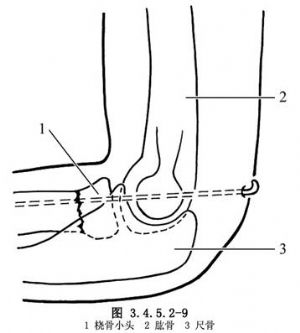

(2)一般不用內固定,特別是兒童。如復位後橈骨小頭極不穩定。可將肘關節屈至90°,從肱骨下端的後方鑽入一根1~1.5mm克氏針,穿過肱骨小頭及橈骨小頭進入橈骨幹髓腔內,用以固定骨折。剪短針尾並折彎埋於皮外(圖3.4.5.2-9)。再按層縫合切口。